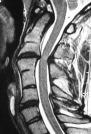

Klippel-Feil Ağustos 2011 Klippel-Feil Sendromunda Myelopati